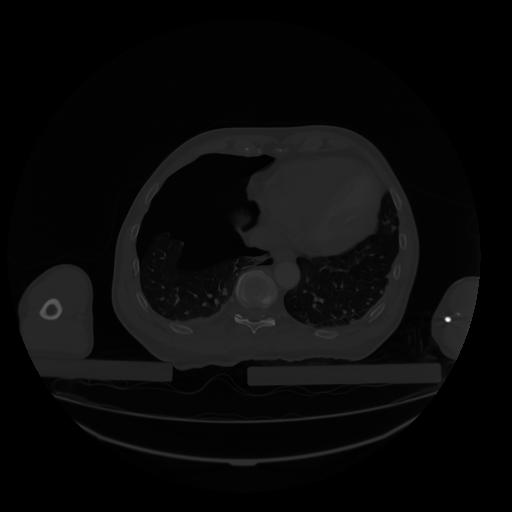

28 CUERPO,CE,Vol,2.0,CUERPO,,